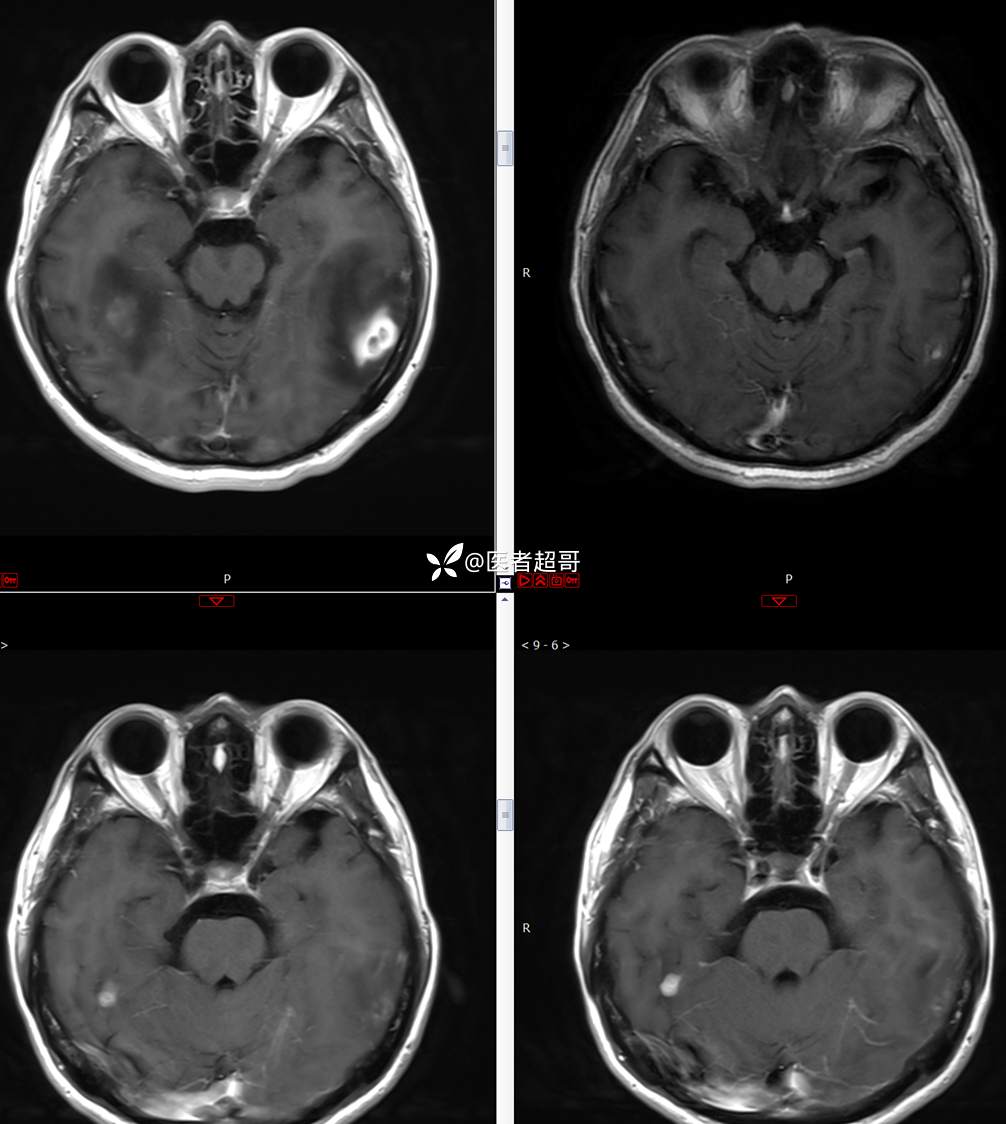

【影诊笔记773】头痛、头晕10天,CT、MRI齐全,请高诊!

主 诉:头痛、头晕10天

现病史:患者10天前无明显诱因感头痛、头晕,伴记忆力减退,无恶心、呕吐,无肢体抽搐及肢体活动不灵等,于我院就诊,行颅脑MR示颅内多发占位,现患者为求进一步治疗于我院就诊,以“颅内占位”收入我科。患者目前神志清,精神可,饮食、睡眠正常,体重无明显变化。

既往史:既往急性肝功能衰竭病史.